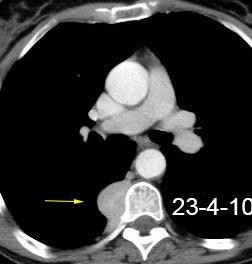

32 años .Preeclampsia a los 19. Hipertensión no controlada. Masa paravertebral sólida que se realza intensamente con afectación ósea.

Yue Y t al. Asymptomatic left posterior mediastinal functional Paraganglioma. A case report. Medicine . 2019